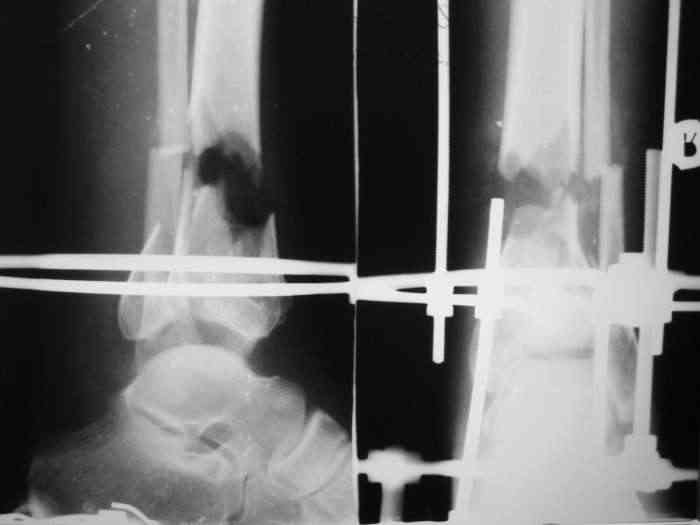

В понедельник в операционной выполнена санация раны с резекцией всех участков кости выступающих в просвет раны, удалены свободнолежащие фрагменты, некрэктомия. Промыто и заполнено салфеткой с некролитической мазью. Дополнительно проведена спица в с/3 голени. "Вытянул" голень до анатомичекой длины. После операции получил неприятный "сюрприз" - дистальный фрагмент б/б кости "разнесло". Снимки выложу завтра. Думаю опять ослабить дистракцию с целью собрать "в кучку" отломки дистального фрагмента, а также для

уменьшения раневой полости (которая меня, по-правде говоря, ужасает).

Состояние раны: постепенно очищается, заполняется грануляциями с участками фибрина. Воспаление мягких тканей вокруг раны купировано. В глубине раны, ближе к дистальному отломку, остается небольшой "гнилой угол" с весьма скудным отделяемым. Две "большие" перевязки в течение недели, с частичными некр- и секвестрэктомиями в условиях операционной.

При закрытой попытке поймать и собрать отломки дистального фрагмента спицами с напайками, удача покинула меня.:-(

Срепонировать суставную поверхность мне не удалось. Только зря прошил ткани, а отломки остались в прежней позиции. Так и подмывало провести спицу через ахилл ... или пойти открыто задним доступом и притянуть винтом. Но смущает один момент: на чем будет держаться резьбовая часть винта, если передная поверхность разбита в хлам? Винт будеть елозить и не даст должной копрессии. Есть ли резон, при нынешнем состоянии раны, пойти на открытую репозицию заднего отдела суставной поверхности?

На мой взгляд необходимо уменьшить дистракцию до полного сближения отломков.Не видно,что в ране-возможно стоит произвести ревизию с тщательной санацией,секвестрэктомией(почти наверняка без этого не обойтись)-судя по снимкам идет воспалительная резорбция концов отломков.

Несколько лет назад у пациентки с подобным переломом результата достичь удалось с помощью сознательного укорочения голени с последующим ее удлинением после сращения.В Вашем случае необходимости трогать малоберцовую нет.

Возникшее расхождение отломков дистального метафиза наиболее вероятно связано с дистракцией в аппарате - лигаментотаксис : задняя тиб.фиб. связка *утянула* задний фрагмент.

Уменьшите дистракцию - всё вернется на свою предыдущую позицию, фиксируйте метафизарные фрагменты спицами 2-3-4 в разных направлениях.

Уважаемый Никита!!! Я думаю в такой ситуации (спасибо за свежие рентгенограммы) будет правильно выполнить :

Радикальную некрэктомию б/берцовой кость с последующим одномоментным закрытием раны перемещённым языкообразным лоскутом. В Последующем- остеотомия в в/з с формированием дистракционного регенерата. Лоскут лучше выкроить с задне-внутр. пов-ти, там кожи больше и она подвижная. Полость надо затомпонировать икроножной мышцей !!!! Ничего страшного нет, всё будет ХОРОШО!!! С уважением Скребцов Владимир